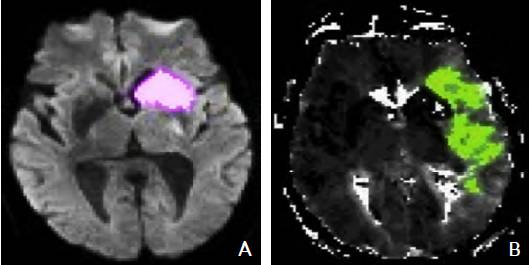

MRI PWI常采用动态磁敏感对比增强技术,通过对比剂团注追踪技术进行动态增强扫描,依靠对比剂磁化率改变引起信号变化的原理成像。经处理后可得出相应灌注成像的参数如CBF、CBV、MTT及TTP等。研究表明,CBF降落和MTT延长是组织缺血的相对敏感指标,但存在过分估计最终梗死体积的可能性;TTP图像上脑灰质、白质之间无明显区别,可以清楚显示病变的范围和边界。虽然目前识别缺血半暗带的方法有多种,但MRI DWI与PWI不匹配区是急诊过程中判断缺血半暗带较切合实际的方法(图4)。一项回顾性研究认为,PWI的病灶面积是DWI病灶面积的2.6倍时早期再灌注的治疗效果最好。

图4 磁共振成像DWI-PWI不匹配区影像 注:A:磁共振DWI序列:高信号的梗死区(粉色标记区);B:磁共振PWI序列:梗死区周围的缺血半暗带(绿色标记区)。DWI:弥散加权成像;PWI:灌注加权成像